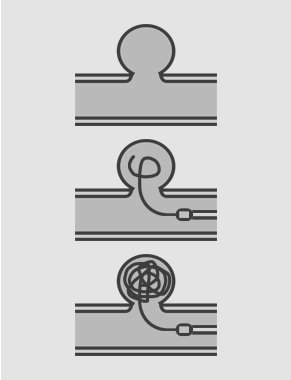

1. 코일 색전술

- 뇌동맥류 색전술은 뇌동맥류 출혈이 발생했거나 앞으로 생길 수 있는 출혈 예방을 위해 뇌동맥류를 정상 혈류로부터 완전히 차단하는 치료방법으로, 동맥류 속에 미세도관을 삽입하고 백금으로 만든 코일을 채워 넣어 정상혈관을 침범하지 않도록 하는 방법입니다.